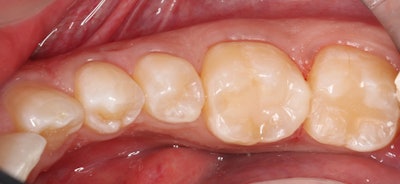

Next, after removing the sprue, the restoration was steamed to remove the lubricant used in the milling process, after which it was seated to verify distal contact.

After verifying fit during try-in, the restoration was removed and polished for about 45 seconds at no more than 4,000 rotations per minute (rpm) using a Meisinger Twist Polisher for hybrid blocks.